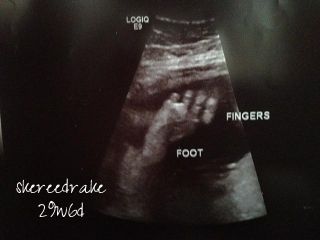

AW: 30 week u/s - PIPs

Went to my ultrasound last night. Elle is measuring at 3 lb. Unfortunately, the u/s tech had put in the wrong due date (two weeks later than my actual due date) and didn't catch it until we were done, so we didn't get accurate percentiles, but I think they were slightly less than average (like 40% or so). Her feet were by her head, and at one point, she started playing with them. So cute!